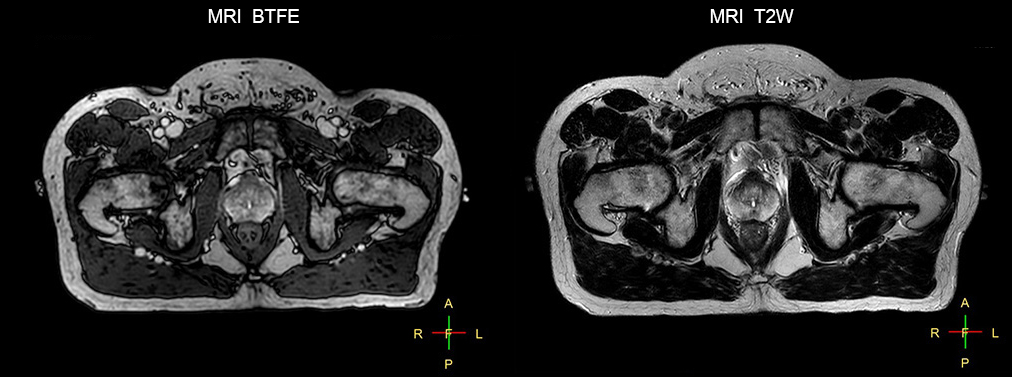

“The biggest problem for CT-based planning, especially in prostate, is you can’t see the cancer very well,” says Dr. Stevens. “On CT it can be quite challenging to see the edge of the prostate especially at the apex. When the edge of the prostate can’t be delineated well on CT, radiation oncologists will increase their margins a little bit so they don’t miss it, but that can also increase toxicity.” “Using MR, the prostate is well delineated. We quickly see the edges of cancerous tumors like in prostate cancer, and as normal structures can be defined, we can optimize the treatment plan to protect these organs and their normal function. This can potentially improve the outcome. And it improves workflow as well. We can contour more quickly, confident that the tumor is going to be in the field.” “The Ingenia 3.0T MR scanner provides high resolution allowing us to make scans fast for the patients. It also gives the potential to include methods like MR spectroscopy and diffusion weighted Imaging, which we’re in the process of doing right now,” Dr. Stevens adds.

“There are some general challenges in RT imaging – even with CT – such as imaging geometry and positioning accuracy. Positioning is extremely important in RT, because we need reproducibility between imaging and treatment position. We also need accurate geometry so we can be sure our treatment plan is properly delivered during the treatment,” says Dr Yan. “The Ingenia MR-RT configuration includes an external laser positioning system for patient alignment and a flat tabletop for imaging the patient in treatment position. Ingenia MR-RT also came with a special QA package for regular monitoring of precision. Our Ingenia 3.0T scanner achieves good geometric accuracy – within a millimeter for most patients – and the phantom measurement is even better,” he adds. “Ingenia’s wide 70 cm bore is valuable to easily accommodate immobilization devices needed in RT,” says Dr. Stevens. “With a small bore MR scanner you can’t get the RT immobilization devices into the scanner properly; the large bore makes it easy to image patients in their immobilization device.”